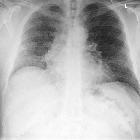

fanciers lung: a case report. Chest radiograph showing bilateral interstitial reticular shadowing with loss of lung volume.